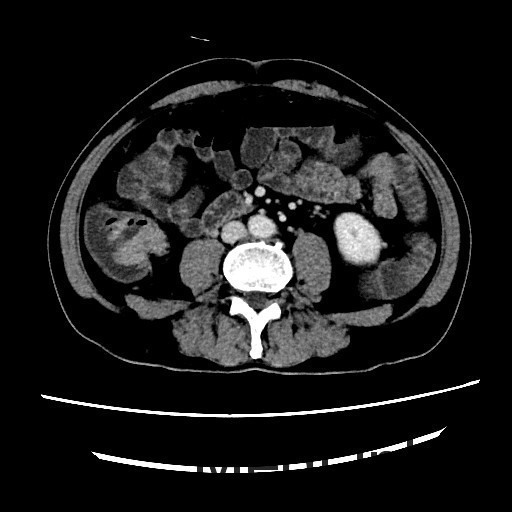

查体:腹平,腹软,肝区、双肾区无叩痛,腹部移动性浊音(-)。肠鸣音4次/分。双下肢无浮肿。 辅查:全腹螺旋CT平扫+增强:1、结肠肝区病变,考虑结肠癌,累及全层。2、直肠及乙状结肠病变,考虑炎症性病变。

讨论:本病例可以在CT冠状位看到结肠肝曲肠壁局限性增厚,属于浸润型结肠癌的表现,CT诊断结肠癌的时候,一般冠状位能够较好的显示结肠全貌,可以比较容易发现病灶,因此平常应先从冠状位发现胃肠道的病灶,再结合横断位诊断。作为影像医生除了报告癌肿,还需要注意一些临床关注的问题,比如癌肿与周围组织的关系,局部有无肿大淋巴结转移,其他脏器有无浸润或转移,在报告中提示这些情况,能够帮助临床选择合适的治疗方案。